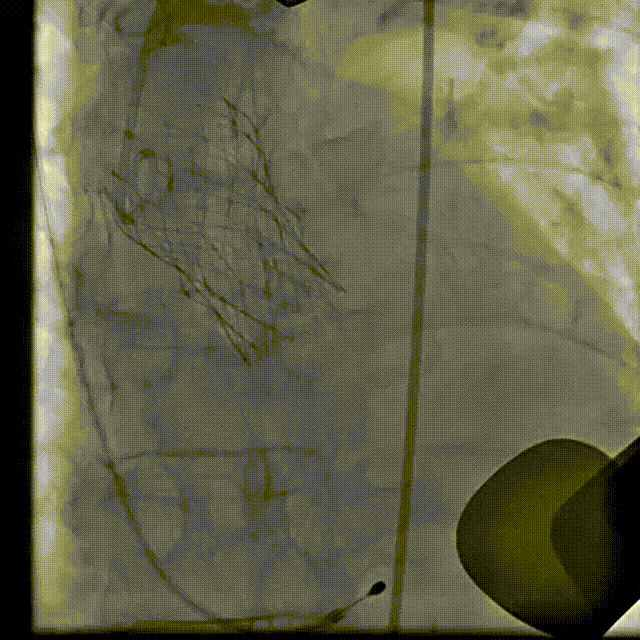

瓣膜交界对齐释放

22 mm球囊后扩

最终造影

• 通过术前影像分析及模拟,术中采用右窦居中投照角度,应用Xcor™独有的极简式交界对齐技术实现交界对齐。

• 本例虽为本中心应用Xcor™产品的第一例临床试验入组,但是通过周密的术前评估以及术中应用Xcor™独有的极简式释放技术,快速实现了从预扩张至瓣膜交界对齐释放完成,释放效果佳,术后血流动力学指标改善明显。